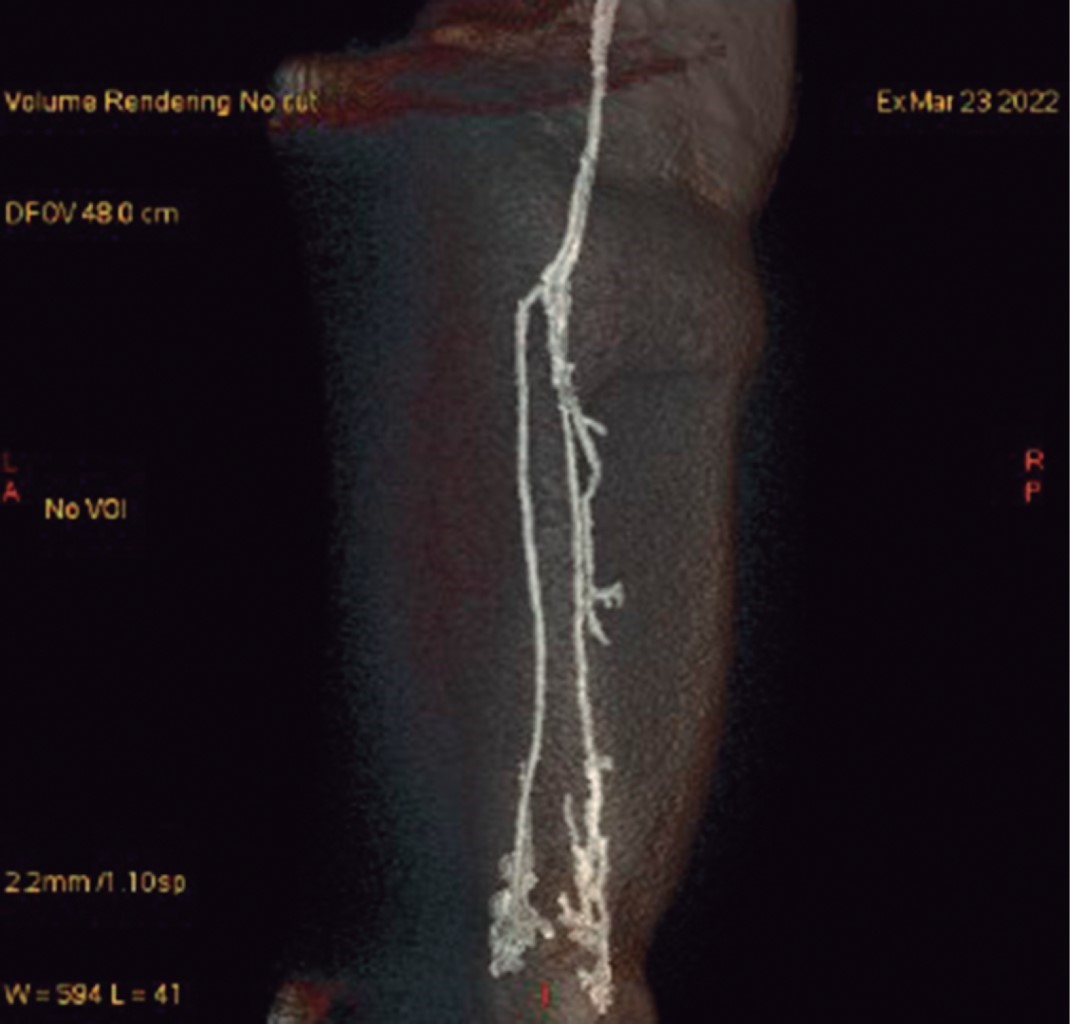

Se continuó abordaje diagnóstico con resonancia magnética de rodilla izquierda en la que se reportó: quiste de Baker, desgarro del ligamento cruzado anterior, derrame articular, contusión y acodamiento del ligamento cruzado posterior, desgarros meniscales complejos (Figura 3). En las imágenes obtenidas se visualizó un quiste de Baker de gran tamaño que no podía ser correctamente definido por las grandes dimensiones del mismo, así como por falta de cortes distales para observar bien el tamaño. Por tal motivo, se solicitó complemento de resonancia magnética de pierna izquierda simple y contrastada con proyecciones angiográficas: trayectos vasculares regulares en todos los segmentos explorados. Se observa desplazamiento de estructuras vasculares que no compromete el calibre ni morfología (Figura 4). Dicho desplazamiento se debe al efecto de masa que condiciona una lesión quística que corresponde a quiste de Baker que se extiende hasta tercio distal de la pierna, el cual presenta heterogeneidad intraluminal, con pliegues parciales de la sinovial que es de grosor uniforme y delgada, reportándose con medidas de 31 × 4.6 × 3.9 cm, con volumen de 289 cm3; posterior a la aplicación del gadolinio, no muestra reforzamiento que sugiera otra patología. Edema en tejido graso subcutáneo, identificando colecciones pequeñas adyacentes a fascias musculares de caras medial y lateral en tercios medio y proximal (Figura 5). Como complemento, se realizaron pruebas de laboratorio para descartar artritis reumatoide; se encuentra factor reumatoide y anticuerpos contra péptido cíclico citrulinado negativos; además, la paciente no cumplía con el resto de los criterios diagnósticos para artritis reumatoide. El tratamiento inicial para la paciente fue manejo conservador con antiinflamatorios no esteroideos e inicio de fisioterapia. Se propuso manejo quirúrgico, así como punción y drenaje del quiste, pero, al contar con los antecedentes cardiovasculares ya mencionados, la paciente rechazó este manejo y se continuó con un tratamiento conservador a base de antiinflamatorios, fisioterapia y vigilancia. A los seis meses de seguimiento, la paciente presenta mejoría clínica y funcional basada en la exploración física y en la sintomatología. Se solicitan estudios de imagen de control, los cuales rechaza la paciente por motivos personales; se decide continuar con seguimiento en la consulta externa con base en clínica y funcionalidad.

Figura 4